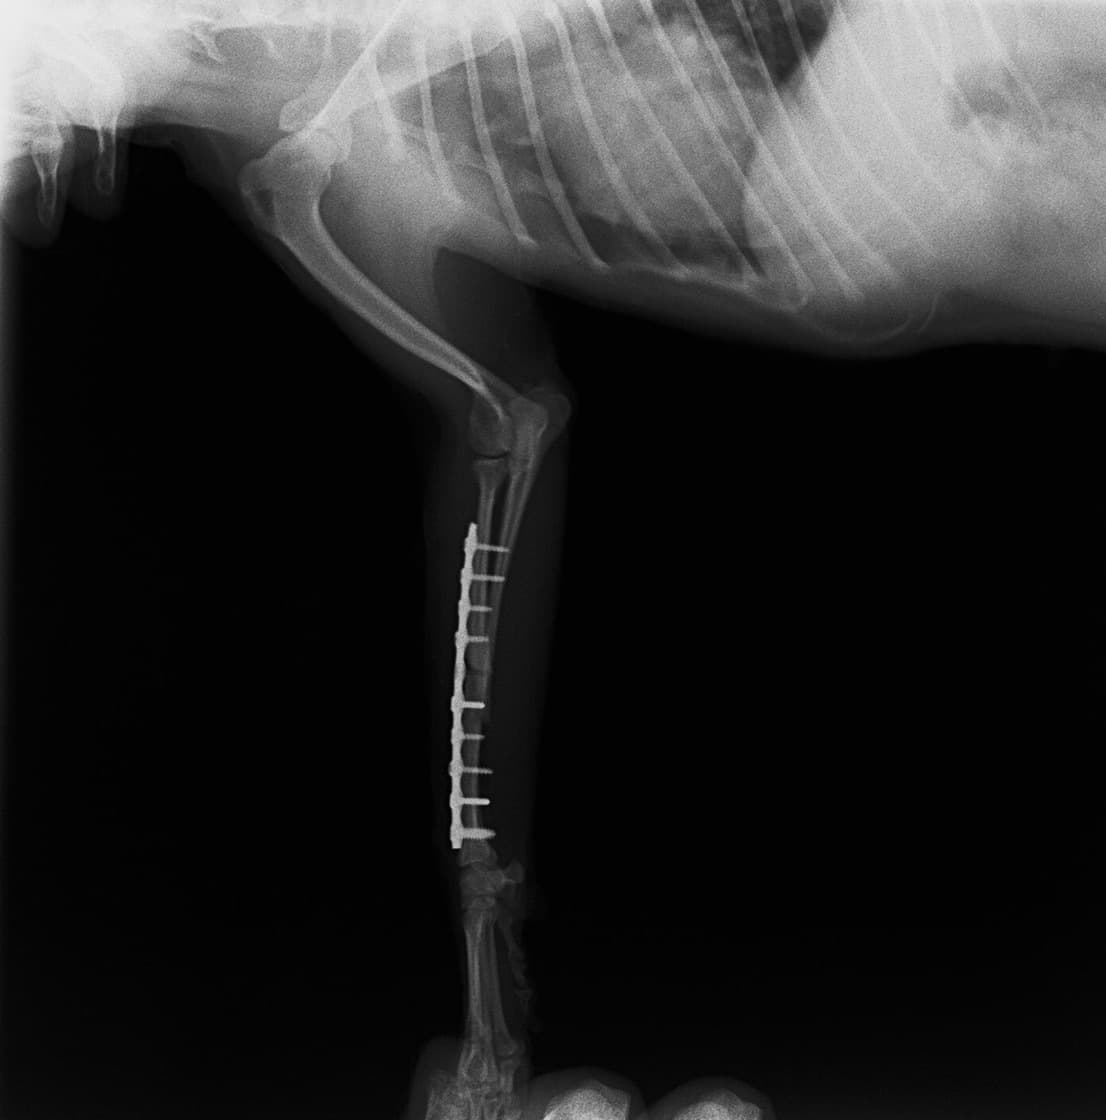

トイプードル 右遠位橈尺骨短斜骨折のALPSによる内固定

Locking Compression Plate

LCPは、スクリュー(ネジ)とプレート(金属の板)をロックする特殊な構造により骨折部位を固定する新しい世代のプレートシステムです。ひとつのホールでロッキングスクリューとスタンダードスクリューの使用を選択できるユニークな構造をしているため、骨折断端間の圧迫を目的とした従来型プレート固定法に加え、高い角度安定性を有するロッキングスクリューを用いた固定法の選択が可能です。従来のプレートシステムでは困難だった部分の骨折や癒合不全の症例に高い治療効果をもたらします。

7.1.5mmと薄いプレートのため、超小型犬にも使用しやすい